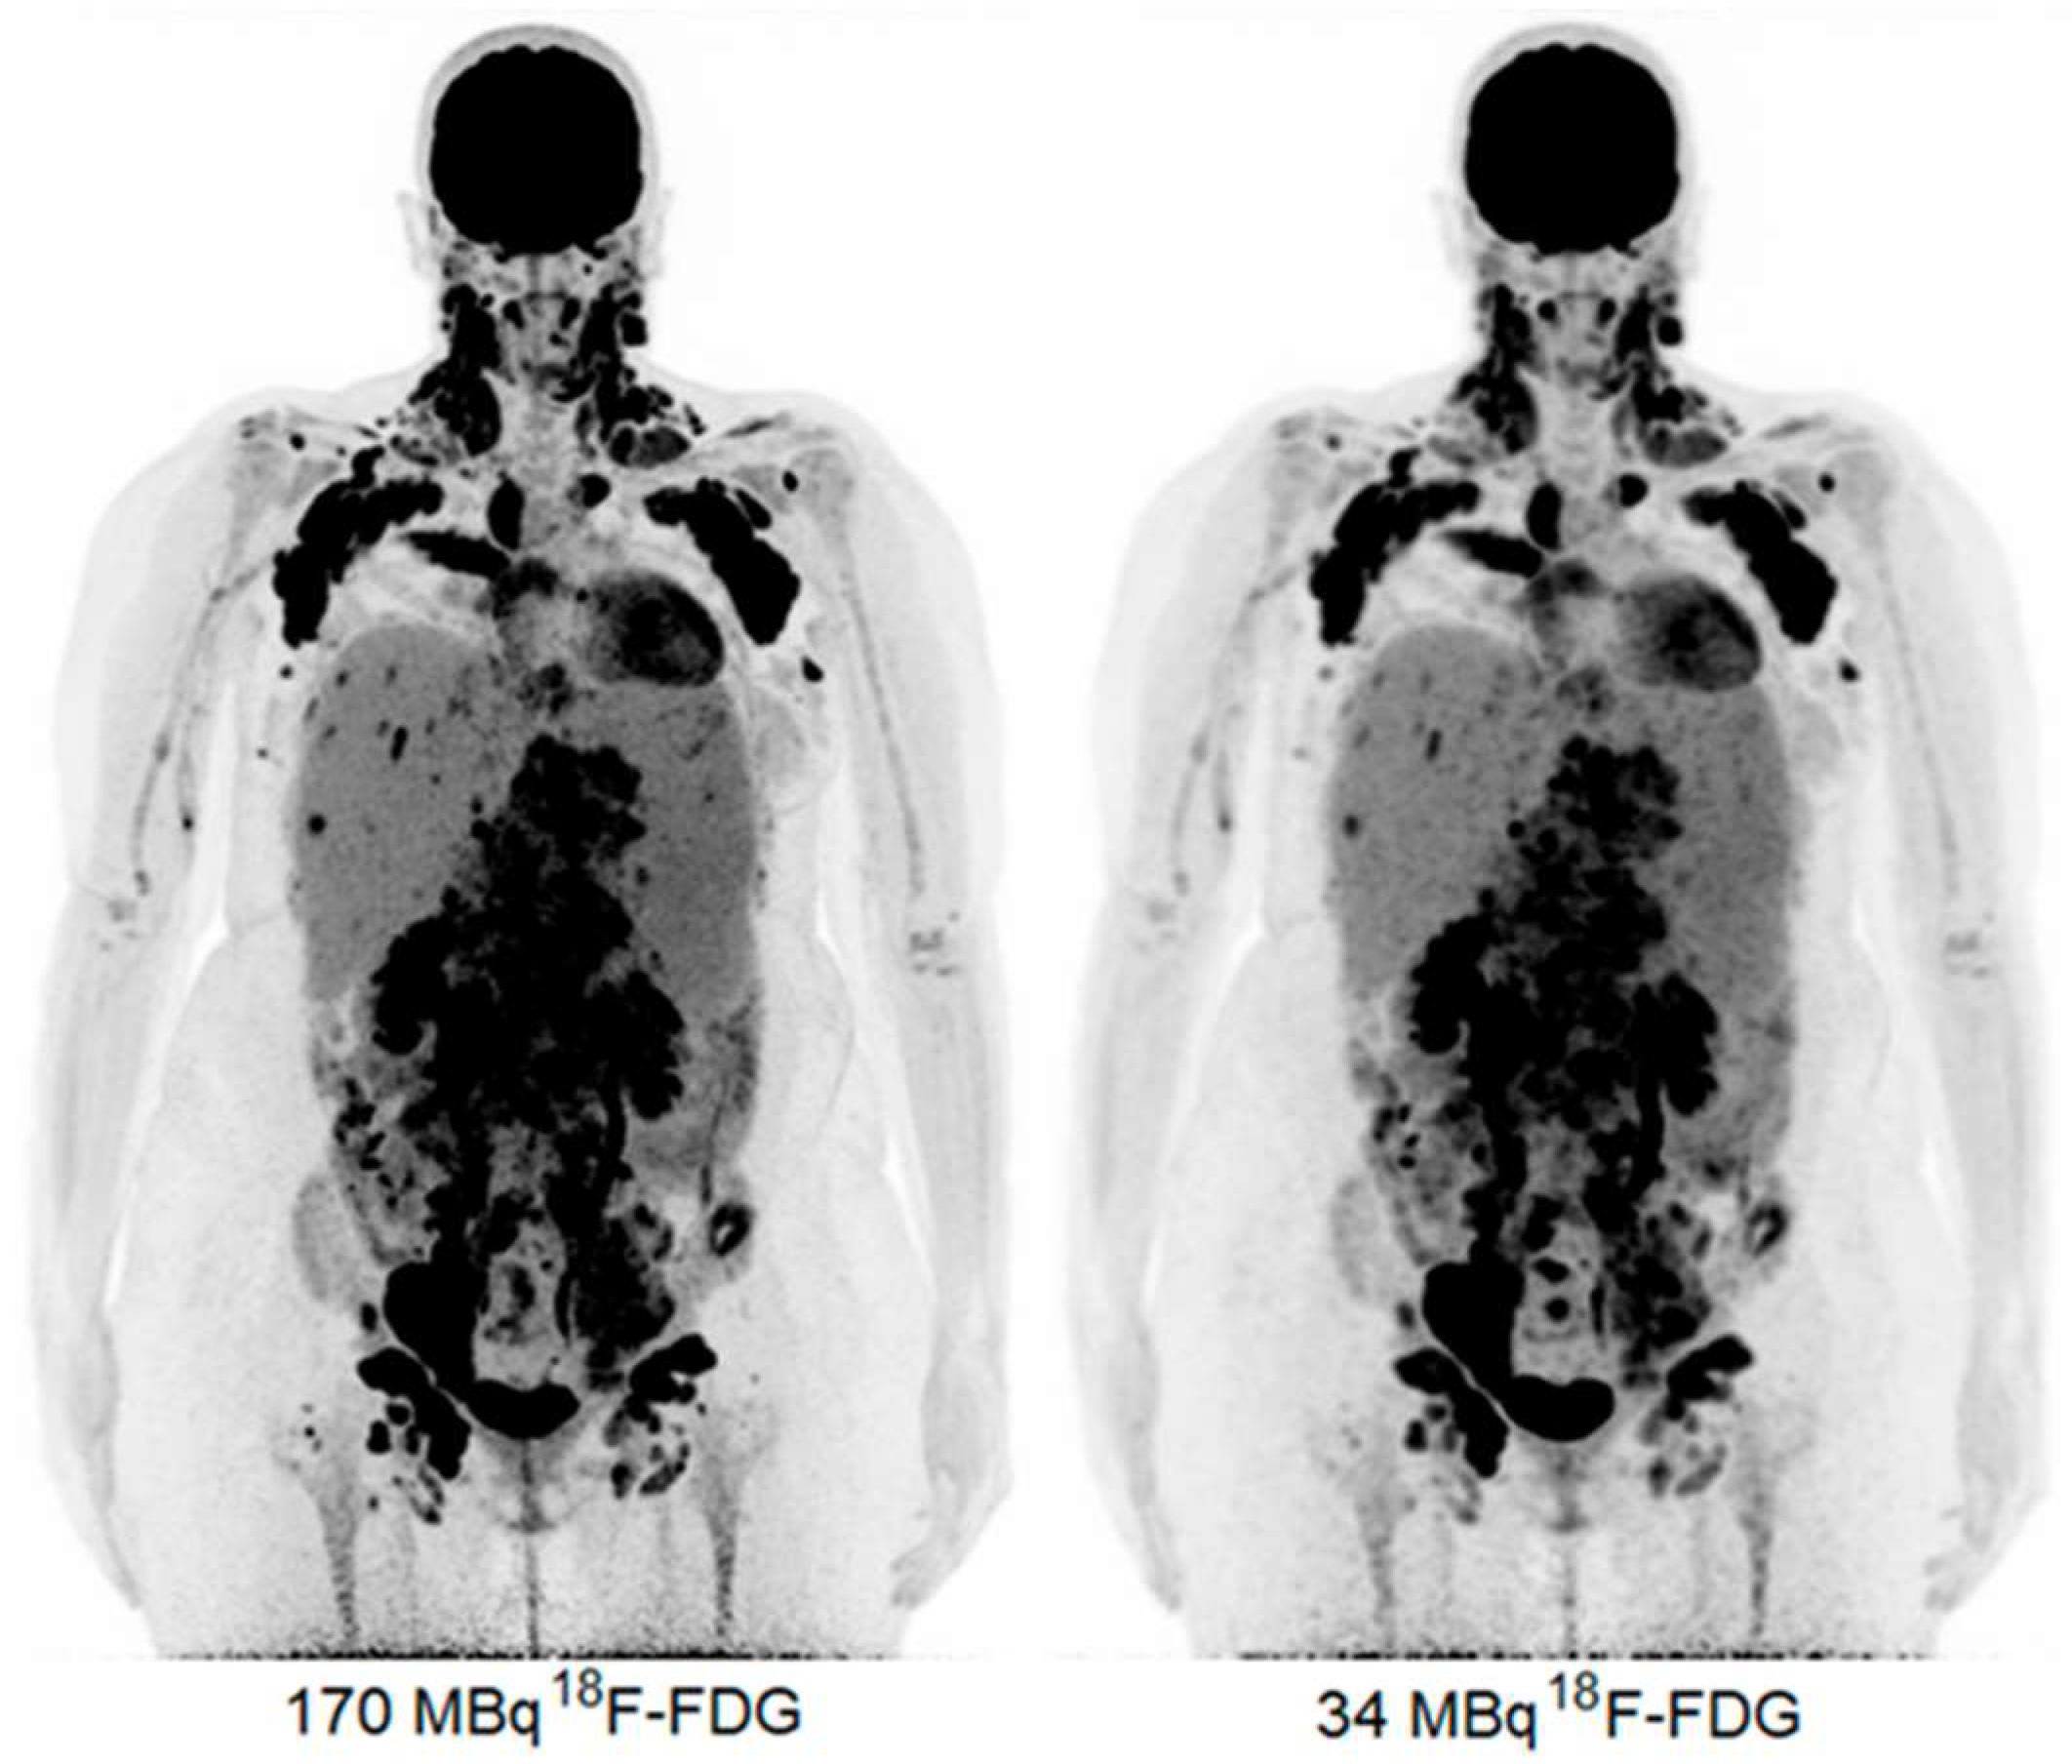

- Sui, X.; Tan, H.; Yu, H.; Xiao, J.; Qi, C.; Cao, Y.; Chen, S.; Zhang, Y.; Hu, P.; Shi, H. Exploration of the total-body PET/CT reconstruction protocol with ultra-low (18)F-FDG activity over a wide range of patient body mass indices. EJNMMI Phys. 2022, 9, 17. [Google Scholar] [CrossRef] [PubMed]

- Van Sluis, J.; Bellido, M.; Glaudemans, A.; Slart, R. Long Axial Field-of-View PET for Ultra-Low-Dose Imaging of Non-Hodgkin Lymphoma during Pregnancy. Diagnostics 2022, 13, 28. [Google Scholar] [CrossRef] [PubMed]